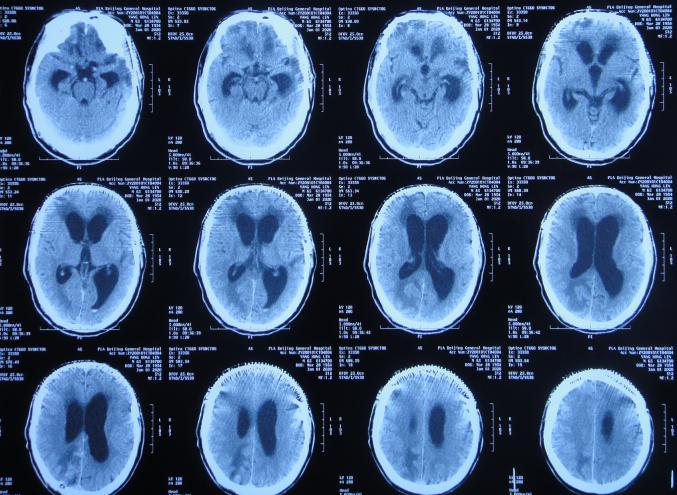

在第4家医院治疗26天,仍间断性发热、大小便*禁失**加重,住院期间曾2次查头颅CT(2020年2月27日( 图-28 )、2020年3月12日( 图-29 ))示脑室仍扩张。

图-28: 2020年2月27日头颅CT

图-29: 2020年3月12日头颅CT

治疗期间给予抗生素,并多次腰椎穿刺,脑脊液培养示无菌,发热虽有好转但大小便*禁失**无改善,且意识变模糊。经当地医生介绍转住入北京北亚骨科医院的李小勇脑脊液科。